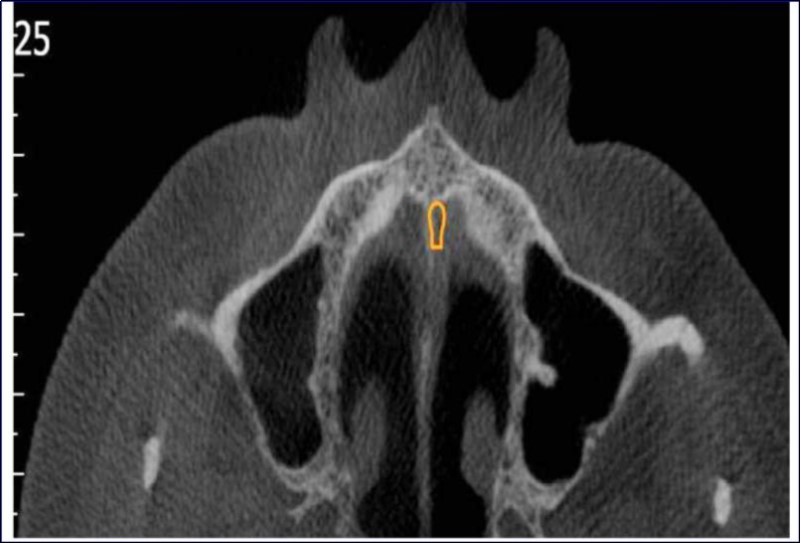

Sinus augmentation procedures were carried-out in 17 patients seeking implant options for oral rehabilitation including 10 for direct and 10 of indirect procedures (n=20, 10 direct and 10 indirect). The study comprised of 43% females and 57% males with a mean age of 46.07 years. A total of 17 patients (20 segments) satisfying the above criteria requiring placement of implants in atrophic maxilla/ increased pneumatisation of the maxillary sinus were selected for the study. The patients were informed about the study including the use of the synthetic graft material and their approval was sought before their inclusion in the study. A written informed consent was obtained from each of the participating patients. For each patient, a detailed case history was taken including chief complaint, history of presenting illness and medical history and personal history. A thorough clinical examination, including systemic and regional examination, was done. Patients with sinus pathology, previous sinus surgeries, chronic smokers, patients under 18 years of age, and with underlying systemic conditions which contradicts any surgical procedures were excluded from the study. The type of sinus lift was decided based on the pre-operative residual bone height evaluated radiographically. The residual bone height was recorded using CBCT scan and a computer based software where the measurements were made from the crest of the ridge till the sinus floor lining. Indirect sinus augmentation was done in patients with a bone height of <9mm but more than or equal to 5mm. Patients with a bone height of less than 5mm were taken up for direct sinus augmentation. The period of edentulousness varied from 6 months to 12 months. Apically tapered, commercially pure titanium implants (Life Care Devices Private Limited Mahim, West Mumbai, India) were used for patients undergoing indirect sinus augmentation. The length of implant was 8, 10, and 11.5 with diameters of 3.5, 4.0, and 5 mm respectively. Patients in the category of direct augmentation underwent the lateral approach procedure and augmentation with an alloplastic graft material. Implant placement was done after 6 months as the second stage procedure. The patients were assessed clinically at immediate post-operatively, and at 1 week, 1 month, 3 months, and 6 months post-operatively. Radiographic assessment for bone height was done pre-operatively and at 6 months post-operatively using cone beam computer tomography. In this comparative study, the measurements were tabulated and statistically analyzed to evaluate the difference in increase in bone height between direct and indirect sinus augmentation procedures radiographically. Orthopantomographs (screening tool) were taken to rule-out other pathologies and as a part of initial assessment. CBCT scans were assessed for pre-operative and post-operative bone height, bone width and bone density. The CBCT scans were obtained from Kodak 9300 which is a hybrid machine using a CS3D imaging software and flap panel detector sensor with exposure parameters of 90 KVp and 10 mA and resolution of 90 microns. The cross sections were made 1mm apart. (Image 1, Image 2, Image 3) The bone height measured pre-operatively using CBCT considered the pre-operative bone height as a measurement taken from the crest of the ridge till the sinus floor and post-operatively, from the crest till hyper-density evident apically. These measurements were standardized as a computer software drawing tool was used. Bone width was taken as the bucco-palatal width at three intervals- at the crest, 3mm from the crest and 6mm from the crest. Bone density was assessed visually by the width of trabecular pattern and were classified based on Misch‘s classification.4 Another additional bone density tool used was the pixel values (the gray scale values) obtained on the CBCT scan, although not reliable, and comparison done pre-operatively and post-operatively. The pixel values contained were a mean of three measurements obtained along the residual bone corresponding with the bone width levels.

Image 1.Routine sequential CBCT scans A and B) Axial sections; C) Cross section; D) Oblique sagittal section; E) 3-D reconstruction; F) Width measurement

Image 2.Axial section of CBCT showing sinus septae

Image 3.Axial sections of CBCT showing sinus mucosal thickening